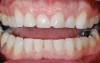

Figure 11  Preoperative photograph of a case in which the patient refused surgery and orthodontics. The treatment goal was to do minimal preparation and use a tough material due to the general medium-to-high risk in every area; obtaining a seal was possible

Figure 11

Figure 12  Postoperative photograph with bonded full-contour restorations in place on the posterior teeth and incisally layered anterior teeth.

Figure 12